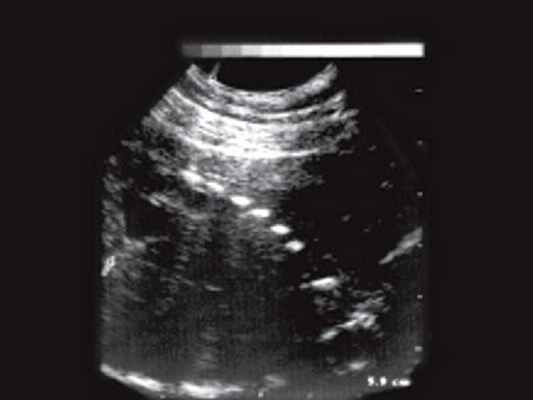

При неизмененной слизистой оболочке прямой кишки и наличии опухолевидного образования в толще ее стенки, кроме лимфосаркомы следует думать о такой патологии, как лейомиосаркома, липома, ангиома, гемангиоэпителиома прямой кишки, воспалительные заболевания. Для липом и сосудистых опухолей характерна более высокая эхогенность, чем при лимфосаркоме. Для лейомиосаркомы характерна низкая эхогенность, но более четкие и ровные контуры [20]. Острые парапроктиты (рис. 3) в стадии инфильтрации имеют более высокую эхогенность и звукопроводимость, неоднородную внутреннюю структуру, а после формирования капсулы они становятся практически анэхогенными, четко отграниченными от окружающих тканей.

Рис. 3. Задний подковообразный острый парапроктит. В отличие от лимфосаркомы имеются четкие контуры образования, расположенного кзади от стенок прямой кишки, хорошо видны плотные стенки, дистальное усиление эхосигнала.